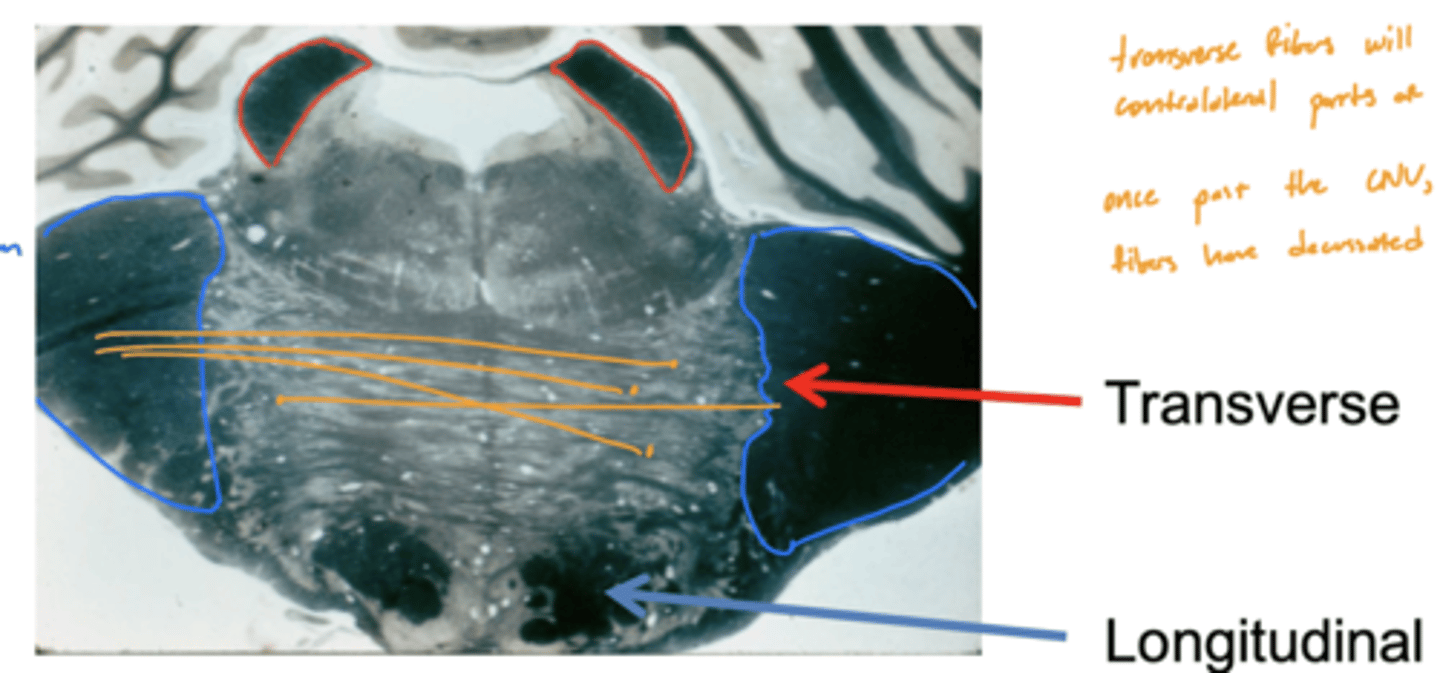

What are the fibers of the base of the pons?

descending motor fibers

longitudinal (descending) fibers

1. corticobulbar

2. corticospinal

What are the longitudinal fibers of the pons?

1. corticobulbar (facial muscles)

2. corticospinal (limbs and trunks muscles)

3. pontine tract

Are the longitudinal fibers of the pons ipsilateral or contralateral?

ipsilateral

Are the transverse fibers of the pons ipsilateral or contralateral?

contralateral (decussate below CN V exiting)

What is the pathway of fibers from the cortex to the cerebellum?

1. Corticopontine fibers (longitudinal fibers)

2. Synapse in the pons

3. Decussation (transverse fibers)

4. Middle cerebellar peduncle

5. Projection to the cerebellum

Are the pons and cerebellum connected contralaterally or ipsilaterally?

contralateral -- transverse fibers decussate underneath (inferior) CN V exiting pons